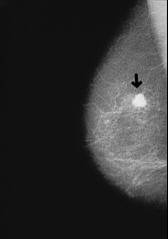

Breast cancer

Organism of blood group AB is vulnerable for most types of cancer like blood group A: all types of cancer which have cells behaving like cells of blood group A. See: Cancer according to blood groups.

Vulnerability for cancer with blood group AB like blood group A

Organism of blood group AB is as vulnerable for cancer like the organism of blood group A (4 Strategien, p.187).

Escargots: Escargots have got a lectin which is working especially against cancer cells of breast cancer and lung cancer which are behaving similar to body cells of type AB. The escargot lectin is eliminating the converted cancer cells by agglutination (4 Strategien, p.187). [This procedure is the same like with blood group A].

-- breast cancer, x-ray photo: http://www.prof-obwegeser.at/brustkrebs.htm